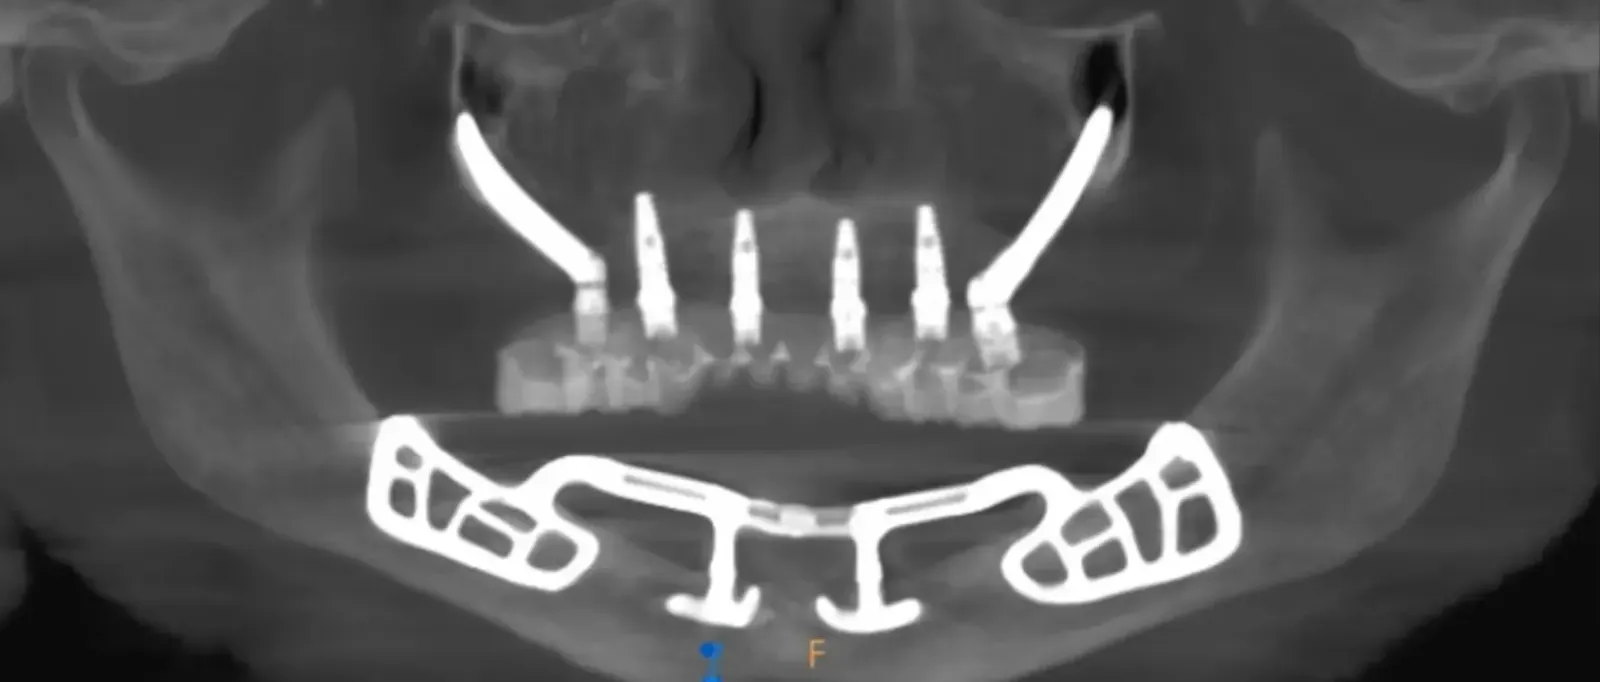

- CBCT-based analysis for anatomical assessment and guided decision-making

Advanced imaging plays a central role in planning arch-level implant treatment. Courses teach clinicians how to interpret CBCT data to evaluate anatomical structures, assess bone volume, and plan implant positioning relative to prosthetic requirements.

Proper imaging analysis helps reduce surgical risk, improve restorative predictability, and support coordination between surgical and prosthetic phases. Understanding how to integrate imaging into the planning process is essential for managing complex cases responsibly.